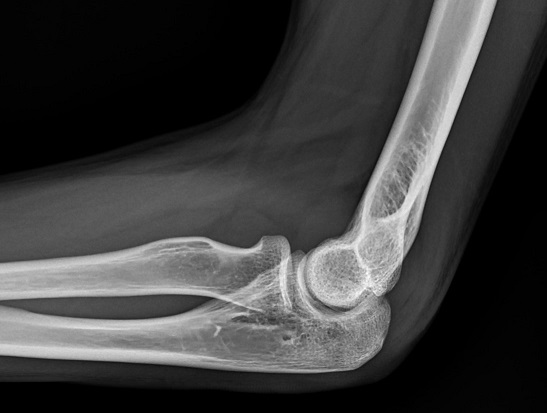

【112-2 醫學(五) 第72題】病人跌倒後被送到急診室,左手肘劇烈疼痛且無法活動。他的左手肘X光片側面照的影像如圖所示,下列敘述何者最恰當?